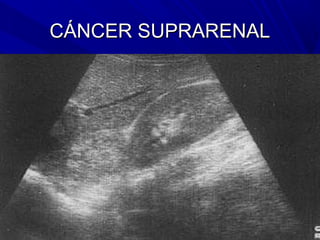

CÁNCER SUPRARENAL